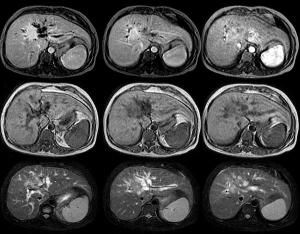

CT表現:

1.末梢型膽管癌:平掃表現為邊緣不規則的低密度占位性病變,一般密度比較均勻。增強掃描於早期時相可見腫瘤邊緣呈輕度環狀增強,晚期時相於腫瘤邊緣顯示為低密度環,而中心表現為高密度,並可見腫瘤末梢側枝肝內膽管擴張徵象。

2cm以下腫瘤常不能顯示上述增強掃描特徵,只顯示整個腫瘤呈輕度增強效應。有時與肝細胞癌難以鑑別。

此外,在末梢部膽管內發育的乳頭狀膽管癌常以末梢膽管的限局性擴張為惟一診斷依據,需注意與肝內膽管結石鑑別診斷。

2.肝門部膽管細胞癌:平掃,腫瘤與周圍肝實質至等密度,肝內膽管呈顯著擴張。增強早期時相腫病至低密度,約 10-15min後,腫瘤中心表現為高密度。這種動態變化有重要診斷價值。

只有壁內浸潤,尚未形成壁外肝內腫塊時,CT增強只顯示膽管壁肥厚,需注意與慢性膽管炎鑑別診斷。但其管壁增厚不均,且顯示僵硬為其不同。